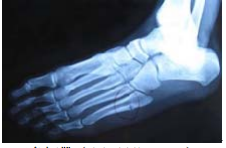

23 如圖所示,造成此種傷害是下列何組織?

(A)三角韌帶(deltoid ligament) (B)前距腓韌帶(anterior talofibular ligament) (C)後距腓韌帶(posterior talofibular ligament) (D)腓骨短肌(peroneus brevis)